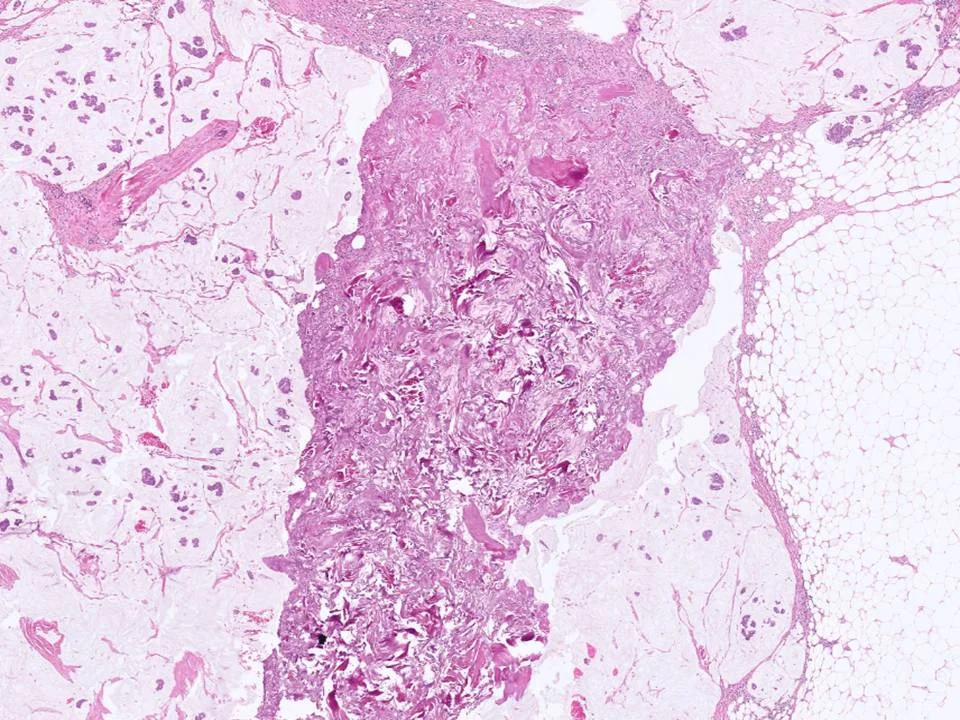

Malignant Phyllodes Tumor

Frond-like projections of cellular stroma covered by epithelium and myopeithelium protruding into epithelial-lined cystic spaces create a leaf-like appearance.

Malignant phyllodes have an infiltrative border (as pictured here), highly cellular stroma, stromal cells with moderate to marked nuclear pleomorphism, and prominent mitotic activity (>/= 10 mits per 10 HPF)